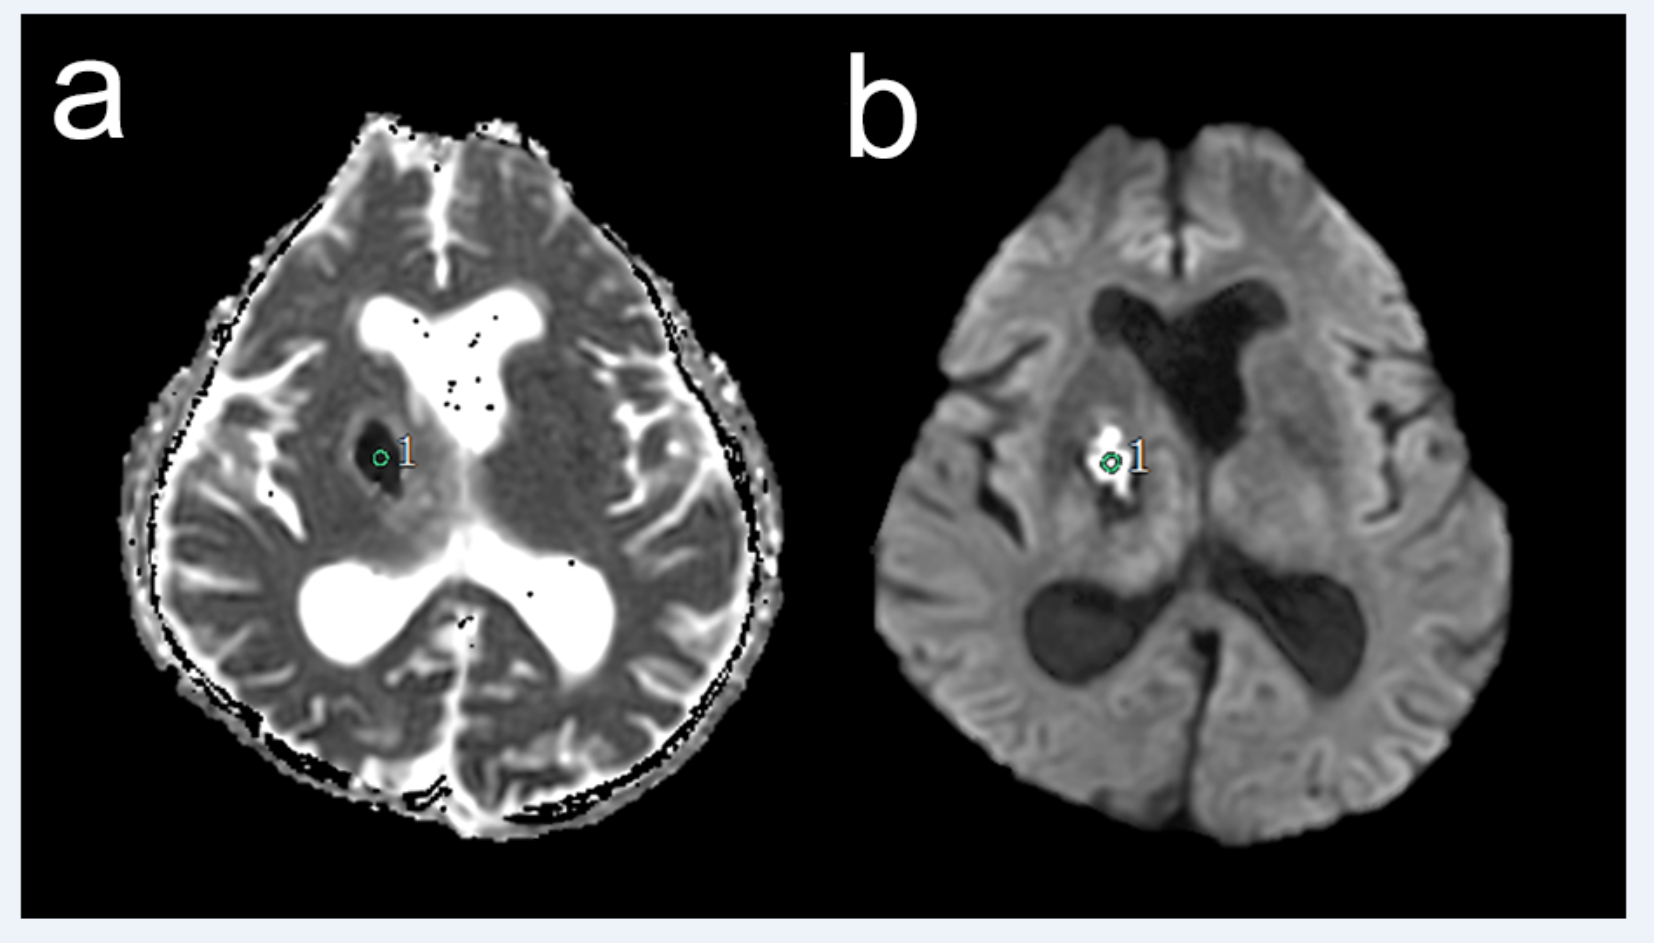

Fig. 1

A circular 5Ā mm2 region of interest was set on an apparent diffusion coefficient (ADC) map (a) and diffusion-weighted imaging (b) centered around the diffusion-restricted area for calculating ADC values using SYNAPSE VINCENT software.